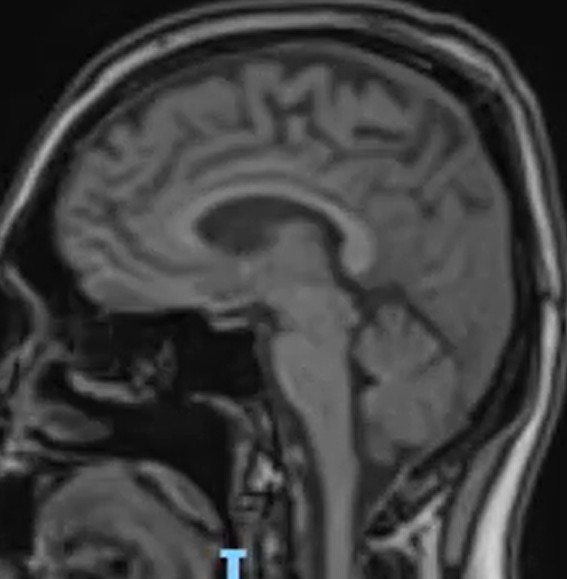

Method: A 37-year-old man with history of controlled Epilepsy who suffered from the subacute onset of cerebellar ataxia and uncontrolled seizures. Abnormalities was found in the cerebellum on initial brain MRI (Fig1,2) and we performed lumbar puncture and other neurological test included infectious, vascular and immunological which were negative. Oligoclonal bands were positive and Cerebral Pet showed cerebellar, frontal hypometabolism and focal hypermetabolism suspect thyroid nodules (Fig 3).

MRI reduction of cerebellum volume in sagital T1